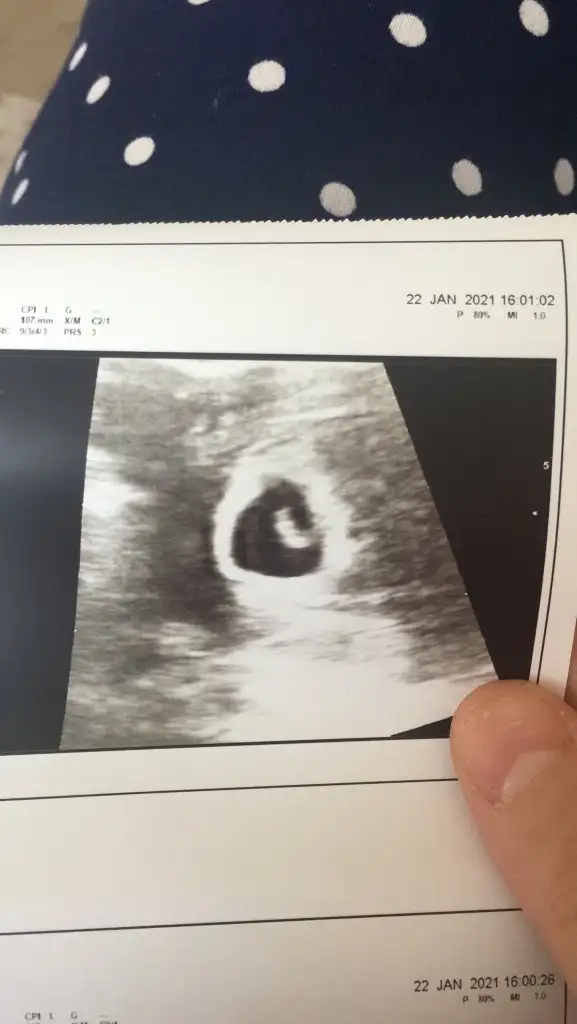

İlk koyduğum ultrason vajinal 5 haftalık, ikincisi görüntü kalitesi daha düşük olan karından 6 haftalık 🥰

• 747FCF6B-325E-4BF7-B5DA-5C3BB6168B83.webp

747FCF6B-325E-4BF7-B5DA-5C3BB6168B83.webp

28,1 KB · Görüntüleme: 278